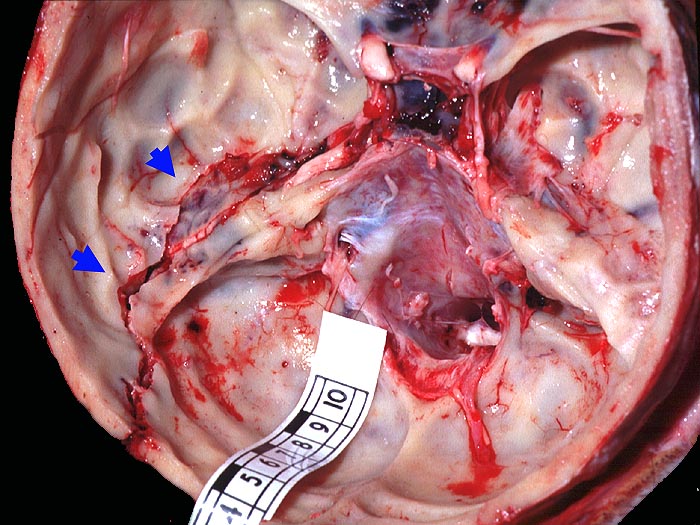

Befund

Pathologischer Befund